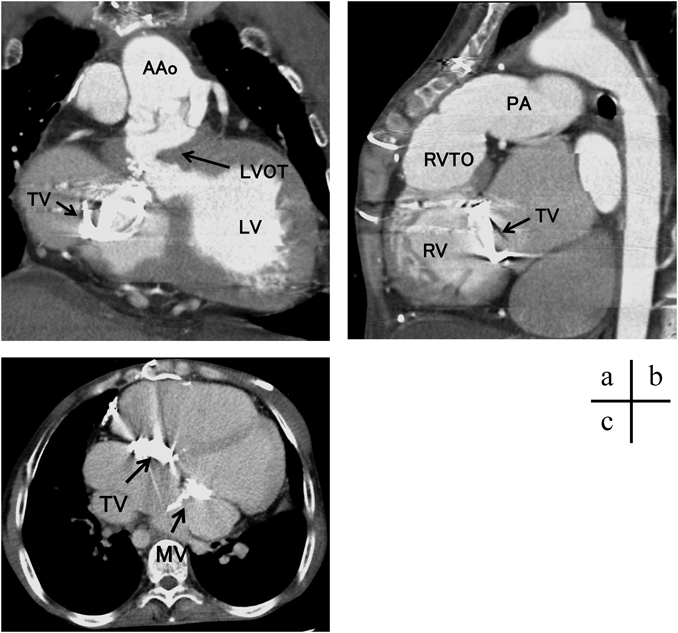

Fig. 3 Preoperative MDCT

a: Coronal image from anterior to posterior showing LVOT stenosis. b: Sagital image from left to right showing sternum pushed up from behind by RV and RVOT. c: Axial image showing 4 chambers and TV and MV. RV, right ventricle; RVOT, right ventricular outflow tract

内臓逆位である.ダブルスイッチ手術後で大動脈は左,肺動脈は右,右側大動脈弓で両側鎖骨下動脈はoriginal Blalock–Taussig shunt後で閉塞.左側優位の両側上大静脈で下大静脈は椎体の左側で心房に還流し(Fig. 2a),左腸骨静脈は閉塞していた.大動脈弁下の左側を中心に著明な心筋の張り出しを認め左室流出路狭窄を形成していた(Fig. 2b, 3a).右室および右室流出路から肺動脈は拡張し胸骨を押し上げ(Fig. 3b, c),両心室はほぼ同等に拡大していた(Fig. 3c).